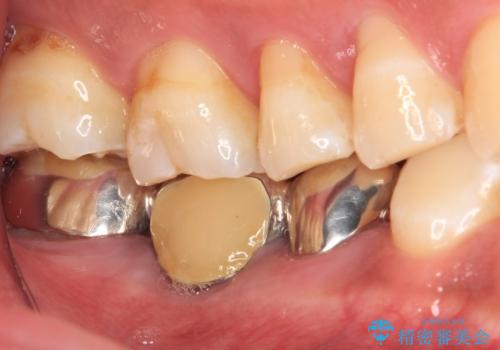

- 以前他院にて、保険診療で治療した金属のブリッジをやり替え希望の患者様です。

奥歯であっても、大きく笑うと金属色が目立ちます。

金属ブリッジを除去し、虫歯を完全に除去し、形を整え、

精度の高いシリコーン材料にて型どりをしました。